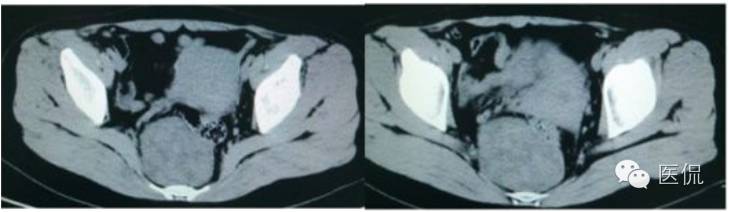

女,37岁,体检超声发现盆腔包块一周。无其他异常。

CT平扫(CT值23HU)